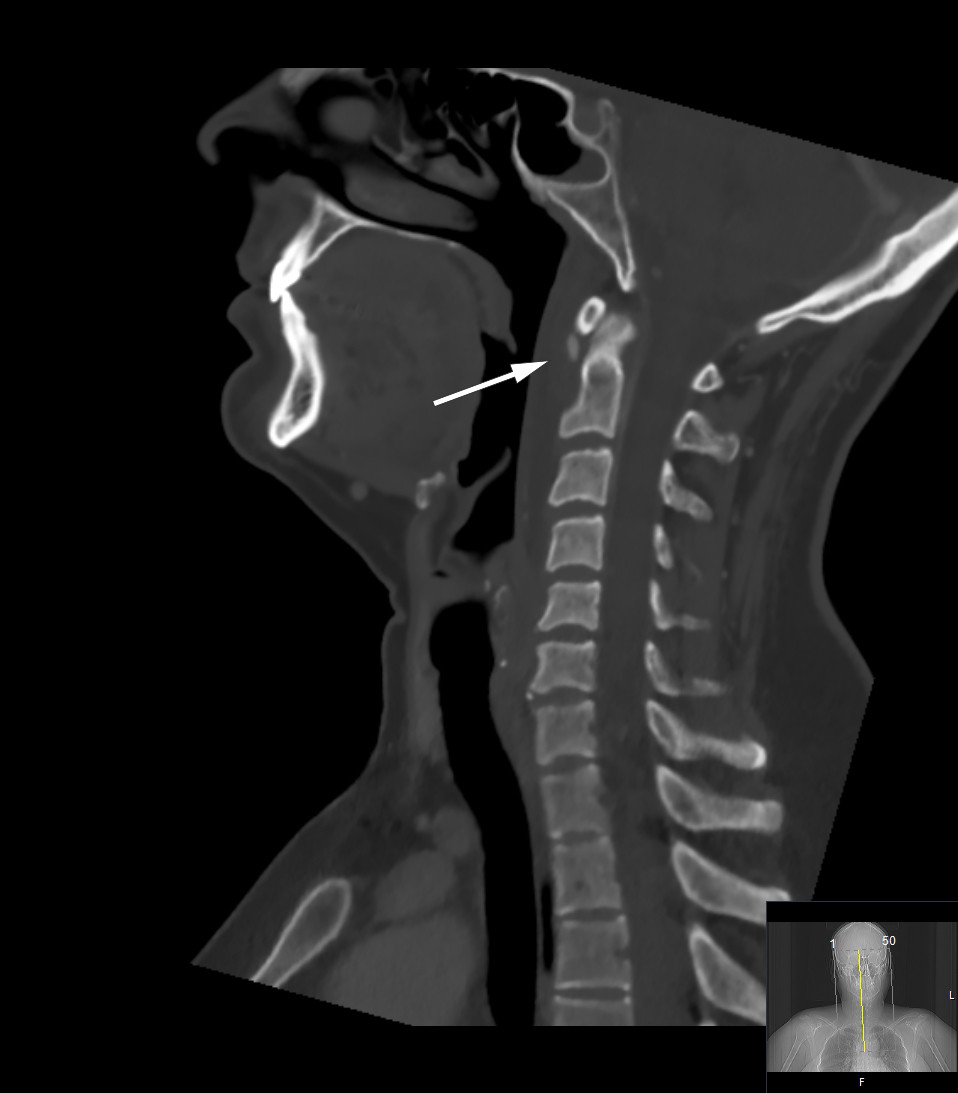

A retropharyngeal abscess was suspected, and the patient was referred for a cervical CT with intravenous contrast. This revealed a thin collection of fluid in the retropharyngeal space and a small, round calcification at the lower edge of the anterior arch of atlas (Figure 1). The typical radiological features of an abscess were absent, with no contrast enhancement around the fluid collection, nor gas bubbles or lymphadenopathy.

The condition may mimic several other infectious conditions, such as retropharyngeal abscess and spondylodiscitis. Imaging is essential for diagnosis, as this case report illustrates. The gold standard is cervical CT with intravenous contrast, which reveals the pathognomonic calcifications in the superior fibres of the longus colli tendon at C1–C2 (1–4) – as seen in our patient (Figure 1).

The amount of calcium can vary and does not correspond to the degree of inflammation (2). Secondary inflammatory changes may also be present, such as retropharyngeal effusion and oedema in prevertebral soft tissue, as seen on both CT and MRI in this patient (Figures 1 and 2). In patients with retropharyngeal abscess, contrast enhancement would be expected around the fluid collection, and possibly gas bubbles and local lymphadenopathy; these will be absent in cases of calcific tendinitis (2, 4). Our patient was nevertheless given antibiotics, as infection could not be completely ruled out.